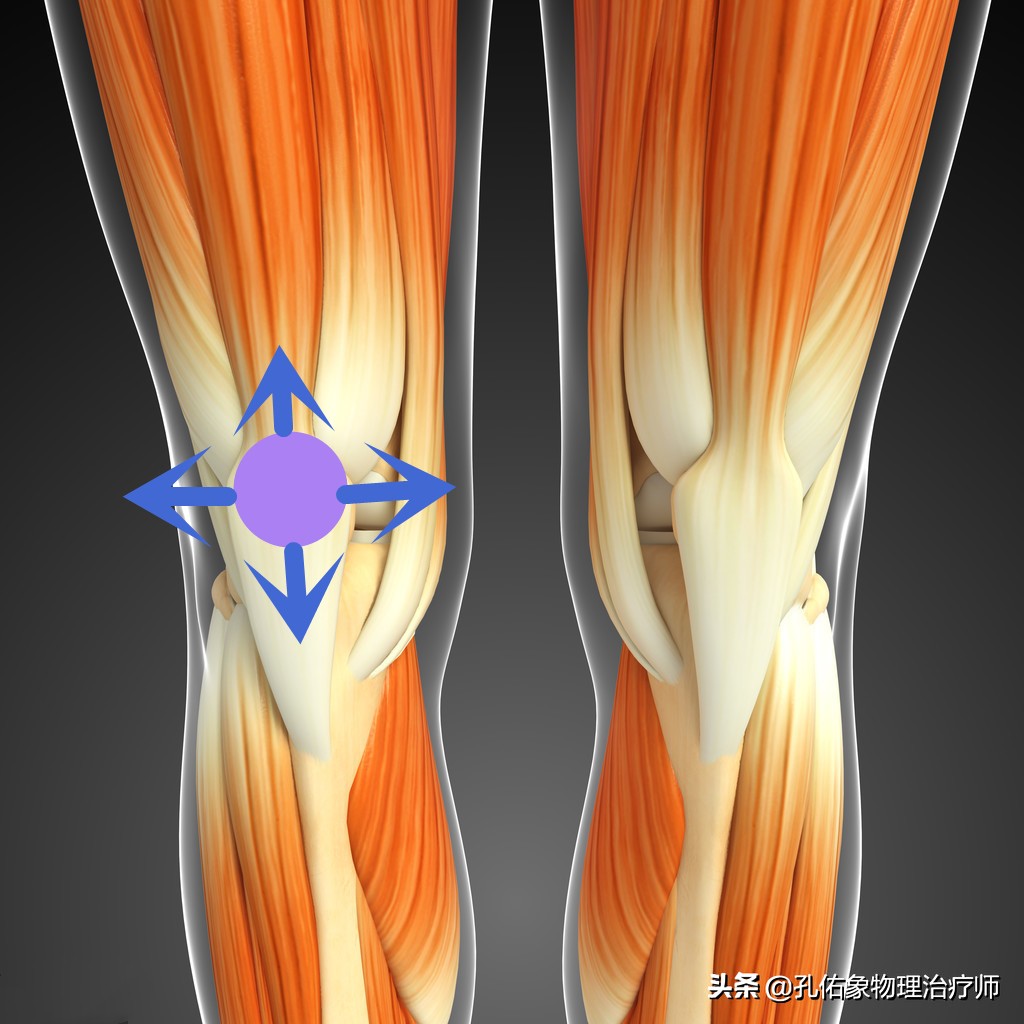

- 膝盖骨的活动度

完全把膝盖伸直,两拇指放在膝盖骨的外侧缘,向内侧推移膝盖骨。一般将膝盖骨的四分之一宽度定位1度。在正常的情况下,膝盖骨的内移程度在1-2度之间;若是超过2度,就说明膝盖骨的活动过大,小于1度就说明膝盖外侧的支持带紧张,即膝盖骨内移受限检查阳性。

我们有必要进行Q角的测量是否正常?它跟膝内翻、膝外翻有直接的关系,反应了大腿上骨盆的问题或是大腿肌肉力量减弱,更直接反应了膝盖骨往内侧移动范围变小的力学关系。如果Q角增大,一定会影响膝盖骨的运动轨迹,大大增加了膝盖骨下面的软骨软化的风险。

第二步:该怎么治疗

到这里呢,治疗相对就很简单了,因为有前期的精准检查评估判断,你是哪里的肌肉软组织紧张?是哪里的肌肉软组织弱?导致膝盖骨的不稳定,偏移了正常的运动轨迹。只需要根据力学去强化和放松即可,当然理念方向找对了,治疗方法相对不固定,会很多的。

比如说,常见的大腿内侧斜肌和内收肌的离心力量强化训练,臀大肌的离心强化训练;阔筋膜张肌和髂胫束的放松训练;膝关节的本体感知训练等等。